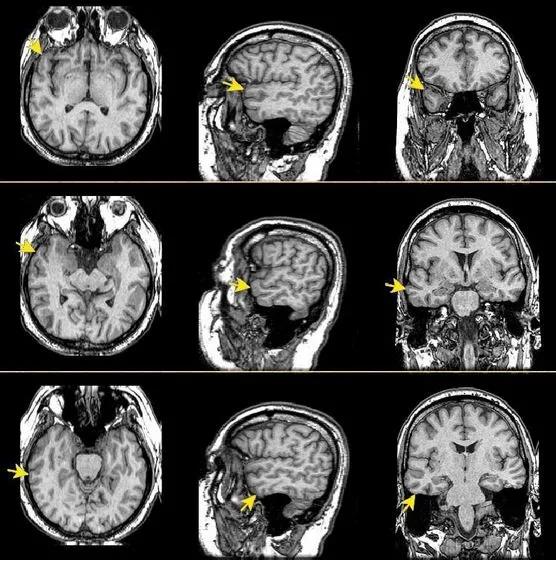

比如下面这个病例,病灶主要在颞叶,额叶只带了一点。但在下面右侧的图,箭头附近额叶和颞叶挤在一起,似乎不是很好区分。

但是在冠状位上,病灶累及额叶和颞叶的范围就明晰多了。虽然病侧颞叶有肿瘤,把外侧沟挤得几乎都没了,但是仔细辨认+结合冠状位其他序列+和对侧对比还是能凑合认认的,特别是健侧特别清楚!